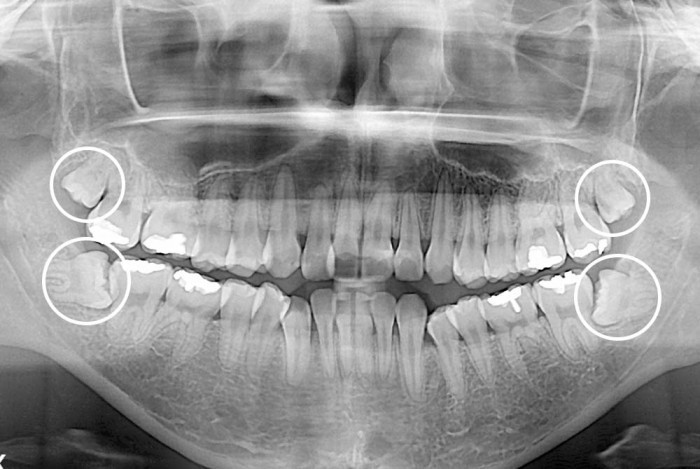

[사랑니] 사랑니

치료후 : 2020-03-23

세종치과는 구강악안면외과학 박사이신 원장님이 발치하는 치과입니다.